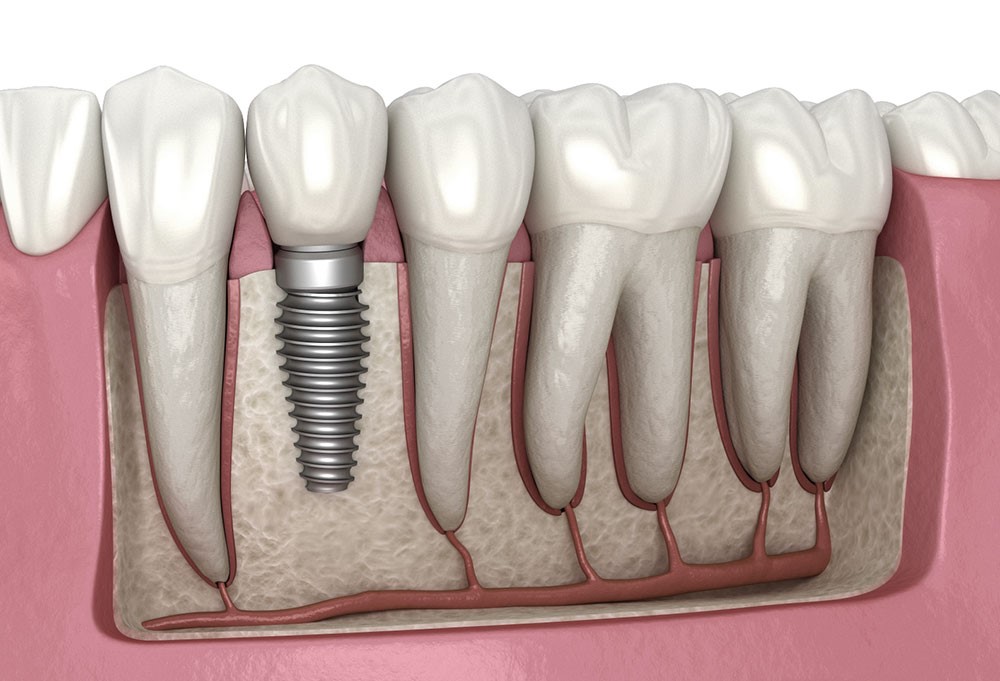

Имплант — небольшой титановый винт с наружной резьбой и внутренней, который устанавливается в челюстную кость и становится корневой частью будущего зуба. Титан отлично приживается, организм его не отторгает, поэтому такой имплант надёжен и долговечен.

Имплант — это точка крепления конструкций, слот интеграции с вашей челюстью через свою внутреннюю резьбу.

На имплант надевается коронка, которая становится новым зубом.

Так выглядит установленная коронка (зуб) на титановый имплант (корень)